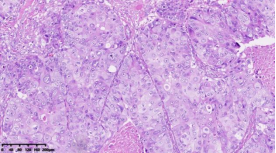

通过进一步基因表达谱测序,对组织形态学和免疫组化水平界定的TNBC亚型的基因变异情况进行分析,筛选各亚组之间的差异表达基因及表达意义探究,结果显示:1.免疫治疗相关的生物标记物MSI-H、TMB-H,作为一个低频发生事件,在TNBC中不太可能常规作为免疫治疗有效性的评估手段;TNBC的MSI发生机制可能与结直肠癌不同、突变热点不同。2. 整个研究队列中基因表达存在明显差异,充分显示了患者个体间差异的存在,从分子水平揭示了TNBC是一种高度异质性肿瘤。3. TP53基因变异率发生最高,提示在TNBC形成中可能扮演非常重要的角色。4. TNBC分型的基因表达聚类分析方面存在差异(图2),这些差异基因参与了多种不同的生物学通路,筛选特异的分子标记物或靶向治疗的靶点以期指导临床治疗。

图2. 基于组织形态学及免疫组织化学标记物的TNBC亚型的基因表达聚类分析